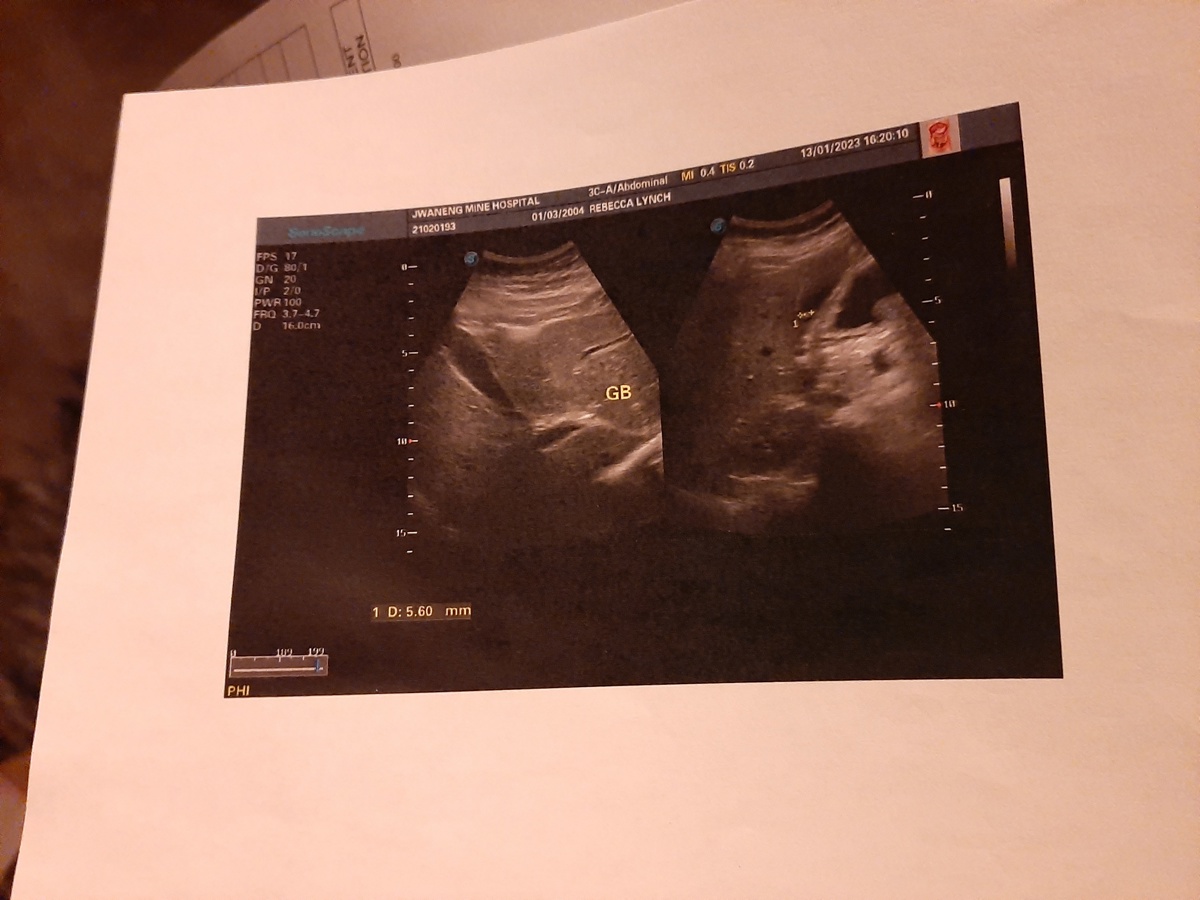

I have health conditions that has made my life extremely limited and painful. I have been diagnosed with stage sarcoidosis and complications of other health problems including: A growth of a tumor in my gallbladder, ovaries and fallopian tube, gastroenteritis and precancerous cells in the esophageal tract. These have lead to me being unable to attend and complete high school, go out to see friends or perform basic tasks because of how sick and in pain I become.

These growths have not been confirmed to be cancer yet as I cannot afford a laproscopy or surgical procedure to remove and take biopsies of my lungs, ovaries and gastrointestinal organs. I was scheduled to have my gallbladder removed and have been scheduled for over a year to get surgeries, but I have never been able to afford any of it.